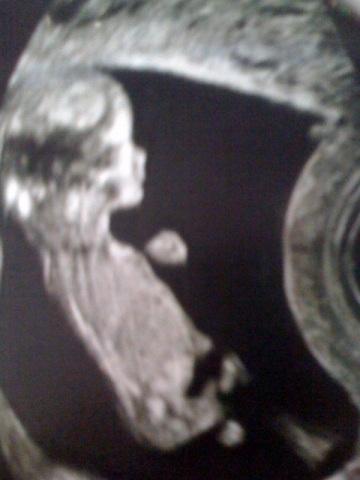

La raison de mon absence mesure aujourd’hui environ 8 cm, me donne des nausées de folies et pointera le bout de son nez pour l’été ! un petit frère ou une petite sœur pour baby boy !!

Echo 12 semaines